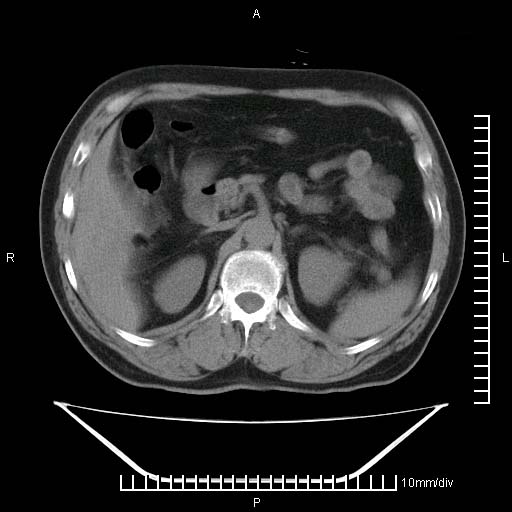

标题: CT25082:肝脏增强:男性,70岁 [打印本页]

标题: CT25082:肝脏增强:男性,70岁

患者以心脏疾病收住院,腹部无明显症状,b超查肝脏有占位。

增强效果不理想。考虑转移,胆囊壁明显增厚,不排除胆囊癌肝转移。

病灶无强化,考虑囊肿。

牛眼征,中心坏死无强化,外缘强化,最外缘又见低密度,考虑转移,与脓肿鉴别

肝内多发转移瘤,右下肺炎症并少量胸水。胃壁增厚建议胃镜,胰尾部“病变”为肠管。

1)肝脏多发性转移瘤(不排除胰尾癌转移所致可能)。2)腹水。3)右侧少量胸腔积液。

增强效果太差了,是手推的吧,不会是团注的,肝内多发低密度灶占位,多考虑为肝ca

ct25082 结果:转移瘤

外院mr结果:胰尾恶性占位。

肝多发低密度灶;轻度强化,较水密度高,考虑转移,不排除肝脓肿